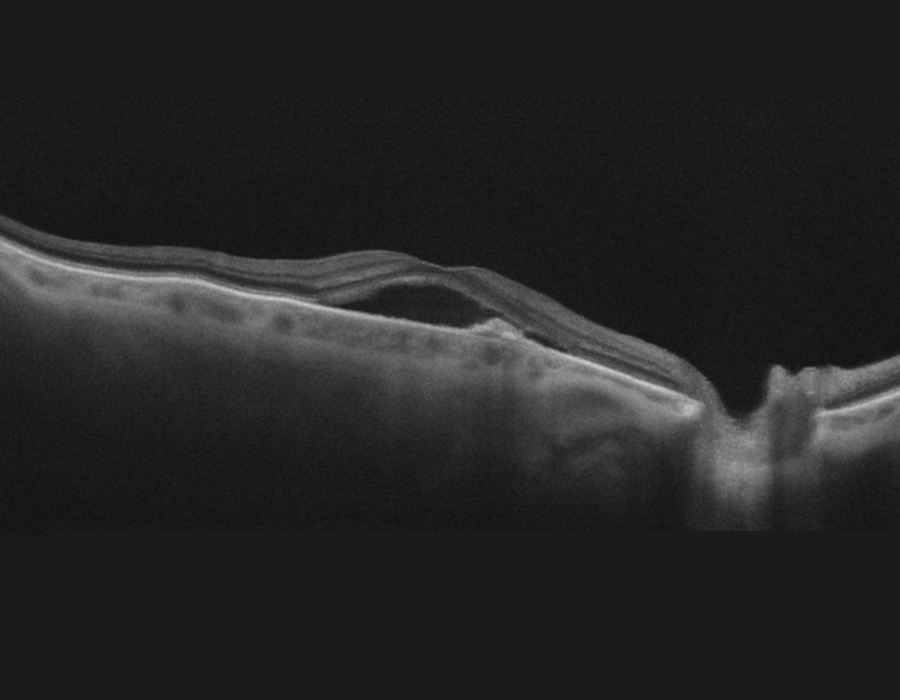

Optical Coherence Tomography (OCT)

- OCT provides cross-sectional images of retinal layers and detects any fluid accumulation, deposition of protein (drusen), and any structural changes in the macula and retina

- OCT is the gold standard for AMD diagnosis and monitoring the treatment

- OCT is essential for treatment planning and monitoring of AMD